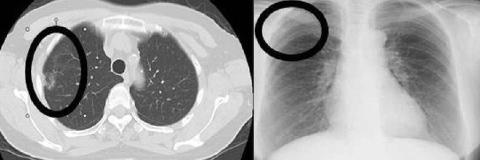

胸部CT検査とは?

肺がんの発見率が2倍に上昇

胸部CTは5分程度の短時間で、胸部の鮮明な断層写真を撮影します。

痛みもなく、通常の胸部レントゲンでは発見困難な早期の肺がんの診断が可能です。胸部レントゲン写真と比較して肺がん発見率は2倍以上です。

被ばく線量は通常胸部CT検査の1/5以下で検査

健診の胸部CT検査の放射線被ばく線量は約1.4mSV(ミリシーベルト)です。

これは通常のCT検査の約1/5以下程度です。